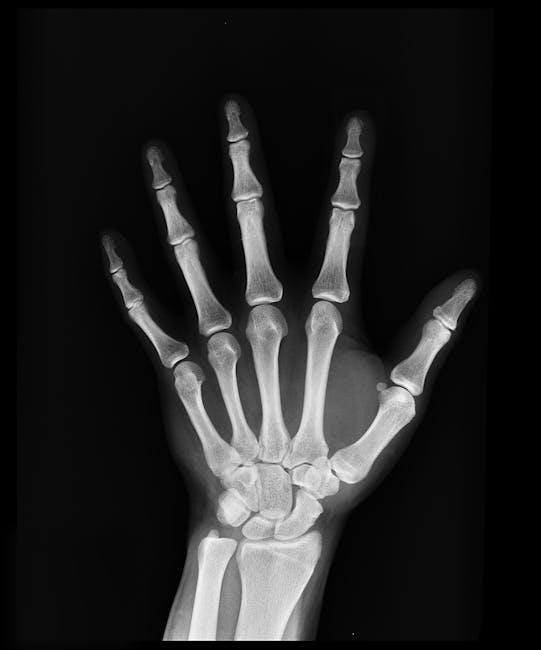

2.3 Symptoms and Diagnosis

Common symptoms of a thumb sprain include pain, swelling, tenderness, and limited movement. Diagnosis typically involves a physical exam to assess thumb stability and mobility. Imaging tests like X-rays or MRIs may be used to rule out fractures or severe ligament tears. Early and accurate diagnosis is crucial for proper treatment and recovery. A healthcare professional will evaluate the severity to determine the appropriate rehabilitation plan.